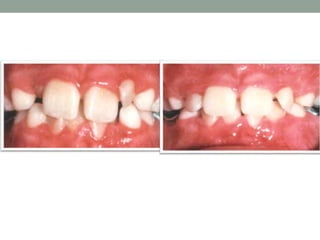

The FunctionalAnterior Cross-bite

(Pseudo Class III)

• #17 Patients who have a functional anterior crossbite exhibit the following characteristics: In centric relation or in a relaxed postural position, the patient presents with a normal facial profile convexity. In centric relation the opposing incisors generally contact edge to edge with the molars separated but in an Angle Class I relation During closing an early occlusal interference causes an anterior shift of the mandible. As the mandible shifts forward into centric occlusion, the incisors are placed into cross-bite and the molars into a Class III relationship.( pseudo Class III )

• #18 Usually result of retarded maxillary growth or maxilla that is backwardly positioned Some of the characteristics they will exhibit are: In centric relation, their facial profile will be concave